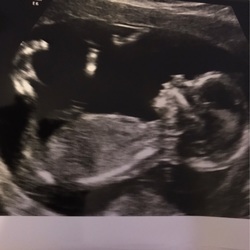

Ach wat heftig ook! Wij ook eerst een leeg vruchtzakje maar bij 6.5 weken een super mooi hartje gezien en zelf kunnen horen. Ik snap er nog steeds niks van, mn lichaam heeft nog niets afgestoten.